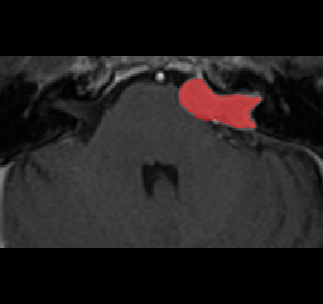

Recently, deep learning methods have achieved state-of-the-art performance in many medical image segmentation tasks. Many of these are based on convolutional neural networks (CNNs). For such methods, the encoder is the key part for global and local information extraction from input images; the extracted features are then passed to the decoder for predicting the segmentations. In contrast, several recent works show a superior performance with the use of transformers, which can better model long-range spatial dependencies and capture low-level details. However, transformer as sole encoder underperforms for some tasks where it cannot efficiently replace the convolution based encoder. In this paper, we propose a model with double encoders for 3D biomedical image segmentation. Our model is a U-shaped CNN augmented with an independent transformer encoder. We fuse the information from the convolutional encoder and the transformer, and pass it to the decoder to obtain the results. We evaluate our methods on three public datasets from three different challenges: BTCV, MoDA and Decathlon. Compared to the state-of-the-art models with and without transformers on each task, our proposed method obtains higher Dice scores across the board.